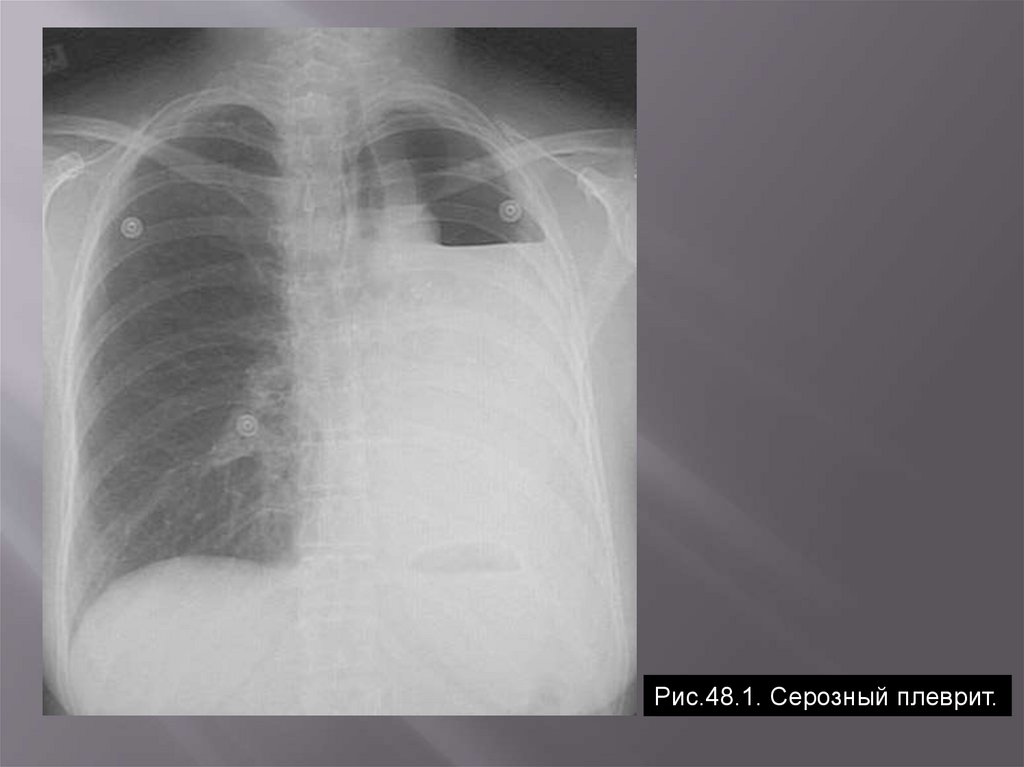

Рис.48.1. Серозный плеврит.

Преобладает фаза экссудации. Выделяют:

Серозное